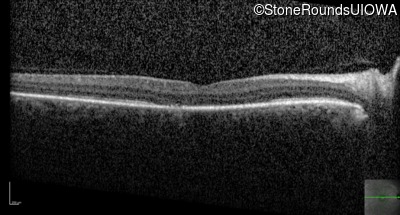

Optical Coherence Tomography - Right - 20/40 -2 sc

Exemplar / OCT Stack